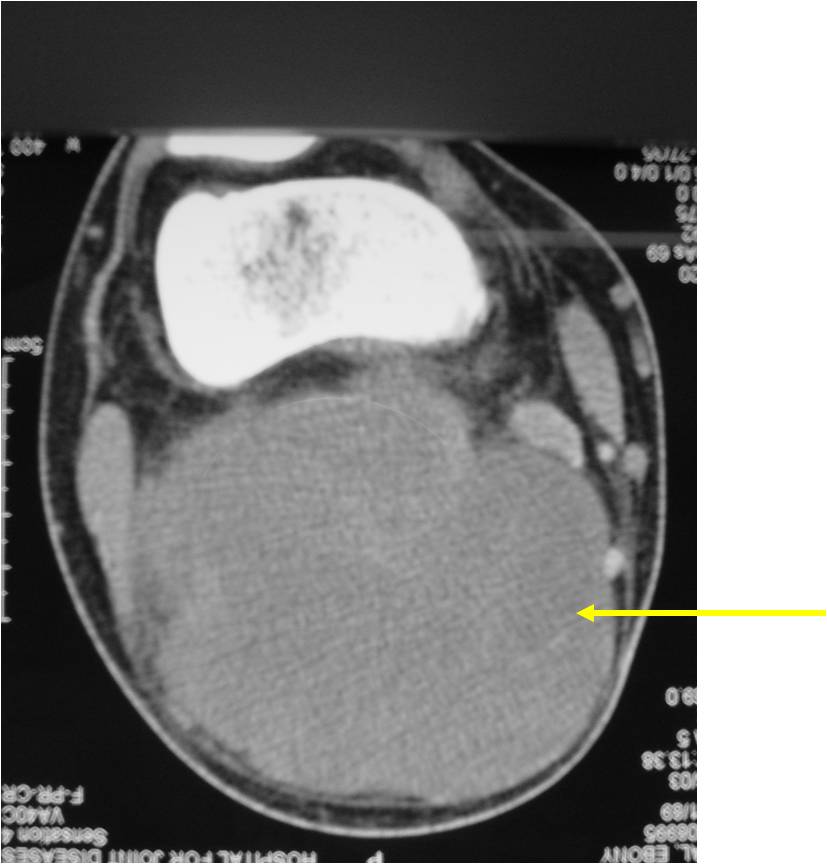

Radiographic Presentation

- Aggressive motheaten to permeative lesion

- Indistinct border in most cases

- Osseous destruction with a soft tissue component

- Chondroid matrix calcification may be present (60-70% of cases)

- Soft tissue mass